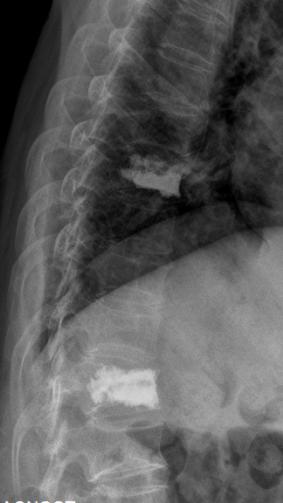

今年6月,63岁的华阿姨因“不慎摔伤致胸腰部疼痛剧烈、无法活动”到我院急诊科就诊,X线检查提示 “胸8.12椎体压缩骨折”,随即收入我院创伤外科住院治疗。完善胸椎CT、MR等后,刘志祥主任带领科室团队迅速为患者制定了个性化治疗方案,并向家属详细介绍病情、各种治疗方案利弊和国内外最新进展后,患者及家属均表示愿意接受微创椎体成形术治疗。

术前核磁共振检查明确T8.12椎体骨折,为疼痛责任椎体;经皮穿刺微创椎体成形术后复查可见椎体高度恢复良好,骨水泥弥散满意。